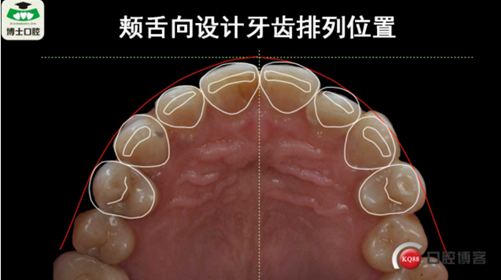

樹(shù)脂貼面與瓷貼面的孰是孰非~牙醫(yī)李強(qiáng)(濟(jì)南博士口腔)

樹(shù)脂貼面與瓷貼面的孰是孰非~牙醫(yī)李強(qiáng)(濟(jì)南博士口腔)

樹(shù)脂貼面與瓷貼面的孰是孰非~牙醫(yī)李強(qiáng)(濟(jì)南博士口腔)